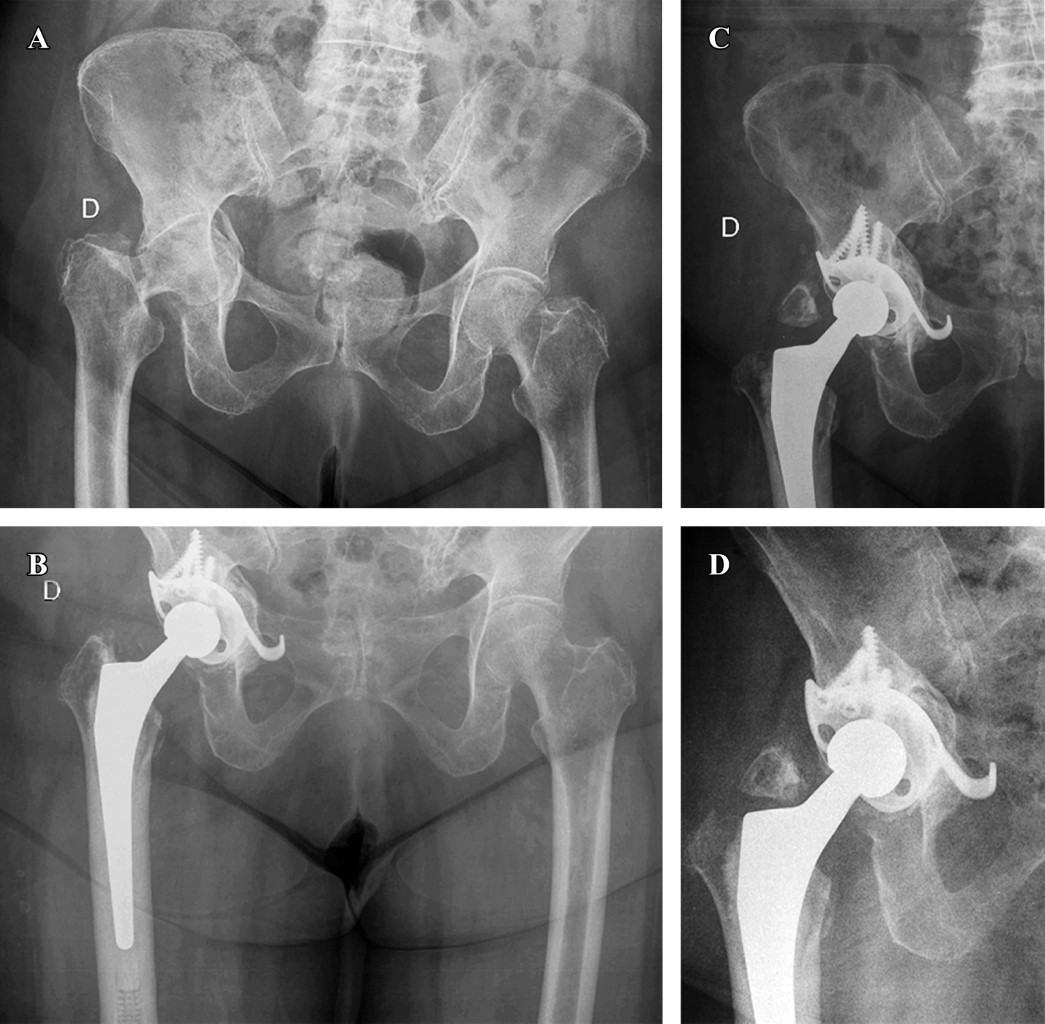

En cuanto al tipo de implante utilizado, en cinco casos se realizó reconstrucción con el concepto "CAGECUP" con una copa de tantalio multihole que permite fijar en múltiples direcciones, media de 56 mm (52-62), fijación con cuatro tornillos (3-5) con cabeza de 36 mm (Figura 1). Las otras dos fracturas requirieron de un implante de reconstrucción tipo anillo de Burch-Schneider (inserto 44 mm, cabeza 28 mm) por elección del cirujano principal debido a que eran fracturas con mayor inestabilidad, un caso de ambas columnas y en una de columna anterior y hemitransversa posterior por el desplazamiento ocurrido entre fragmentos (Figura 2). En todos los casos se utilizó autoinjerto de cabeza de fémur, en uno de los cuales se asoció además a sustituto óseo DBX® (Depuy Synthes) más chips de esponjosa por considerarse autoinjerto cuantitativamente insuficiente. Se implantó vástago cementado en cuatro casos y no cementado en tres (Tabla 2).

Figura 1